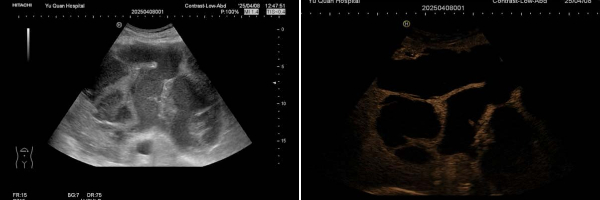

近日,我院超聲診斷科診治一名肝臟巨大囊實(shí)性腫物患者,通過(guò)超聲造影明確診斷為肝膿腫,并立即在超聲引導(dǎo)下實(shí)施置管引流術(shù),24小時(shí)內(nèi)引流出膿液近1000ml,患者癥狀顯著緩解。這一病例展現(xiàn)了超聲技術(shù)在疾病診斷與治療中的“雙效合一”優(yōu)勢(shì),為臨床提供了高效、精準(zhǔn)的解決方案。

影像檢查陷困境 超聲造影“一錘定音”

該患者因在外院發(fā)現(xiàn)肝臟占位入住我院普外科。入院時(shí)腹脹、無(wú)腹痛、發(fā)熱。增強(qiáng)CT和增強(qiáng)MRI均提示肝臟巨大囊實(shí)性占位,但無(wú)法明確病變性質(zhì)。入院后完善相關(guān)化驗(yàn)檢查:白細(xì)胞15.76×*10^9/L,中性粒細(xì)胞計(jì)數(shù)13.84×*10^9/L,C反應(yīng)蛋白128.0mg/L,葡萄糖7.83mmol/L,腫瘤標(biāo)志物(-),患者有糖尿病病史且血糖控制不佳,且入院后已出現(xiàn)發(fā)熱癥狀,考慮肝膿腫可能。普外科請(qǐng)超聲醫(yī)學(xué)科會(huì)診:常規(guī)超聲探查肝左葉可見一囊實(shí)性包塊,大小約19.9x14.2x15.5cm。即刻行超聲造影檢查,實(shí)時(shí)動(dòng)態(tài)觀察該病灶的血流灌注方式:病灶內(nèi)動(dòng)脈期呈典型的網(wǎng)格樣高增強(qiáng),中央可見無(wú)增強(qiáng)區(qū),門脈期及延遲期呈等增強(qiáng),符合肝膿腫的超聲造影表現(xiàn)。

組合1.jpg